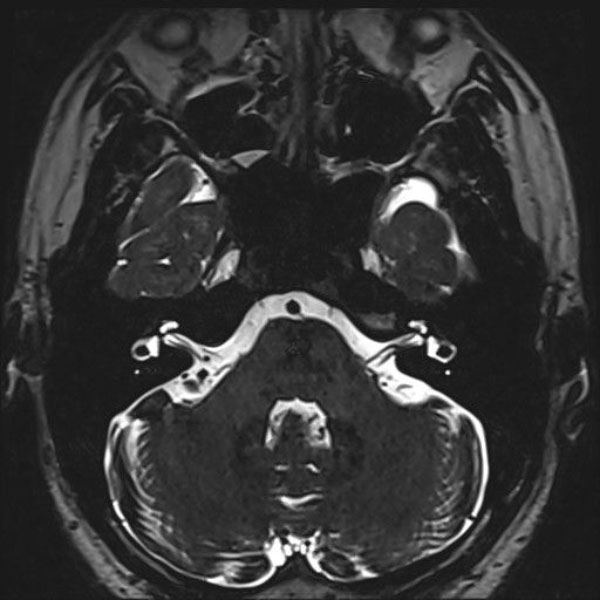

手術前

(MR1)